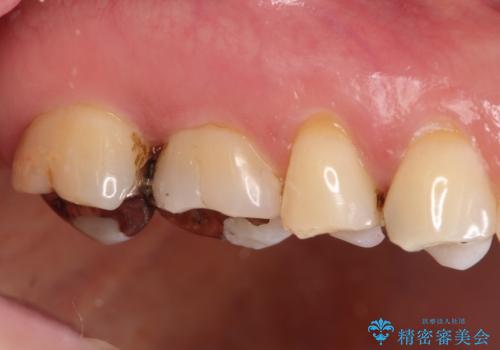

- 銀歯が外れて、中が虫歯になっているところがありました。

虫歯を取り除き、ゴールドインレーを装着する治療計画としました。

ゴールドは目立つという欠点がありますが、適合が良く、割れることもないため、長期的に安定した治療法となります。